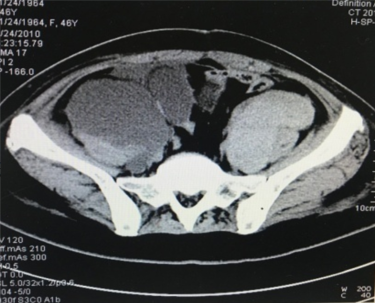

患者2012年2月20日查盆腹增强CT提示新出现左隔下结节;4月23日复查CT结果为:左侧膈下软组织结节,较前增大,考虑腹膜转移;腹膜后小淋巴结,考虑肿瘤复发;阴道残端左上方结节,较前略饱满(图2)。CA-125 117.3 U/ml。

图2 2012年4月23日盆腹增强CT结果